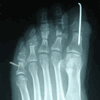

Caso 2: Hallux Valgus del Adolescente

Pie Izquierdo operado